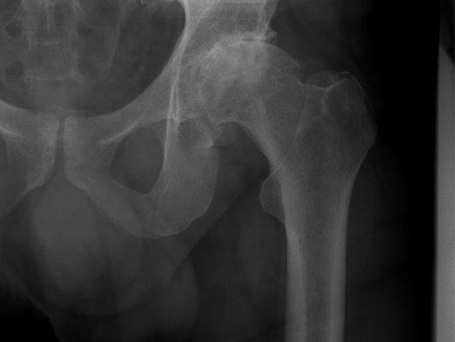

HÜFT-TEP DES PATIENTEN

Deutliche Coxarthrose links

Coxarthrose links, Versorgung mit Kurzschaft-Prothese

Deutliche Coxarthrose links bei einem 56-jährigen Mann, begeisterter Radfahrer, versorgt mit einer Kurzschaftprothese im Herbst 2020.